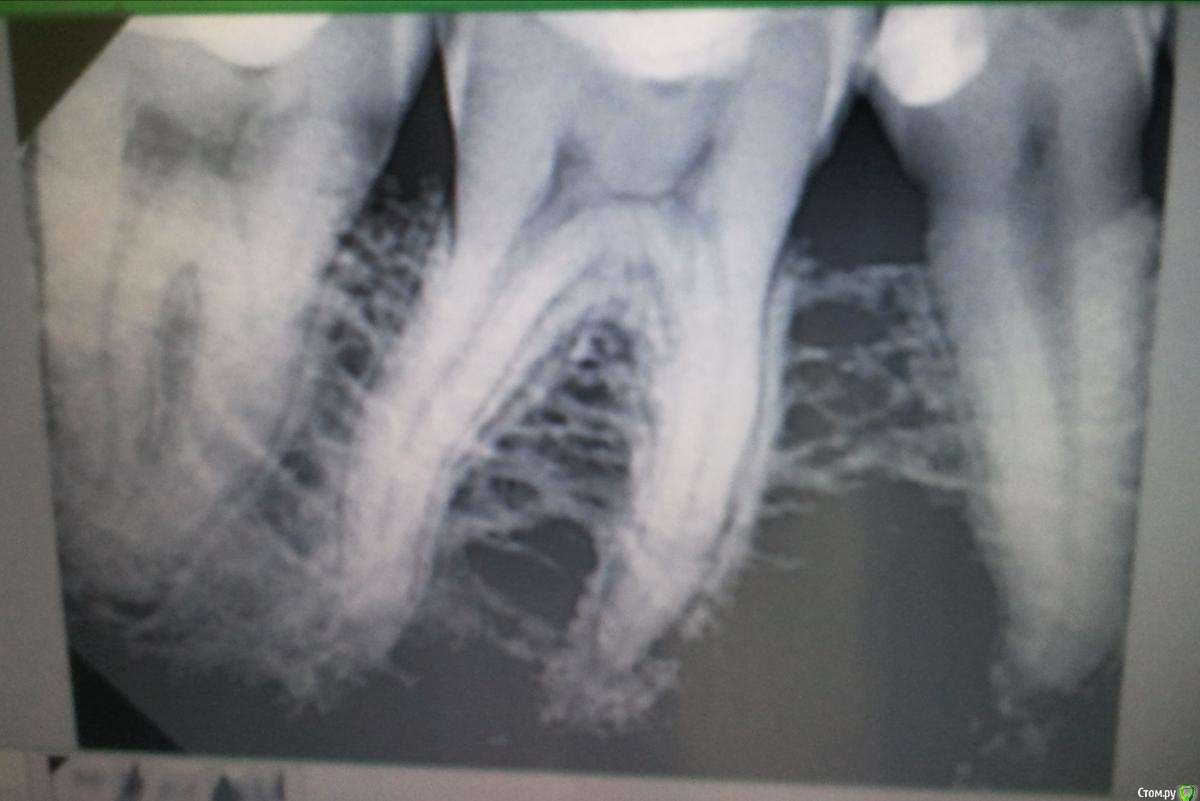

Samuel16 Опубликовано 21 октября, 2019 Поделиться Опубликовано 21 октября, 2019 (изменено) Здравствуйте, постараюсь быть максимально информативным.4 месяца назад провел лечение зубов в бюджетной клинике. Чуть больше недели назад начал болеть 17 зуб, внешне все было целое. На следующий день боль стала невыноимая, записался на ближайшее время и удалили нерв. Вроде облегчение. Но на следующий день начал болеть противоположный зуб (46). Боль усиливалась и через 2 дня боль переросла в распирающую. Пришел в клинику все обьяснил, сделали снимок. Врач сказал что ничего страшного не видит, а боль может быть реакция на лекарство заложенное в 17 зуб. и что лучше пока зуб не трогать. При постукивании выяснилось что болит не только 46 зуб а и 47, хотя он меня никогда не беспокоил. Решил долечить 17 и посмотреть что будет. но сильная боль продолжадась и я пошел со снимком к другому стоматологу. Тот увидел проблему как раз в 47 зубе который никогда не беспокоил. Сказал что там может и нет уже нерва. Для меня это оказалось страным в итоге окончательно запутался. Добавлю что когда ставили пломбу на 46 зуб кариес был глубоким, и ставился вопрос о удалении нерва. Но в итоге сохранили, на протяжении 4 месяцев зуб не болел но был очень чувствительным к холодному...Возможно вы увидите что то на снимке и посоветуете как лучше потупить? Изменено 21 октября, 2019 пользователем Samuel16 Ссылка на комментарий

krokomot Опубликовано 21 октября, 2019 Поделиться Опубликовано 21 октября, 2019 проблемы есть и 6м и в 7м, лечить каналы обоих. 1 Ссылка на комментарий

krokomot Опубликовано 21 октября, 2019 Поделиться Опубликовано 21 октября, 2019 в 6м явный склероз пульповой камеры. это говорит о перераздражении пульпы, а это приведет к склерозу системы каналов и невозможности в дальнейшем качественно пролечить этот зуб и вы попадете на его удаление(зуба), в 7м виден воспалительный процесс на верхушке корня, это говорит об инфицировании пульпы. не забывайте, что я консультирую только лишь на основании вашего снимка, для полного и достоверного диагноза потребуется осмотр и другие методы обследования. 2 Ссылка на комментарий

krokomot Опубликовано 21 октября, 2019 Поделиться Опубликовано 21 октября, 2019 Болит 7й, боль отдает на 6й. Ссылка на комментарий